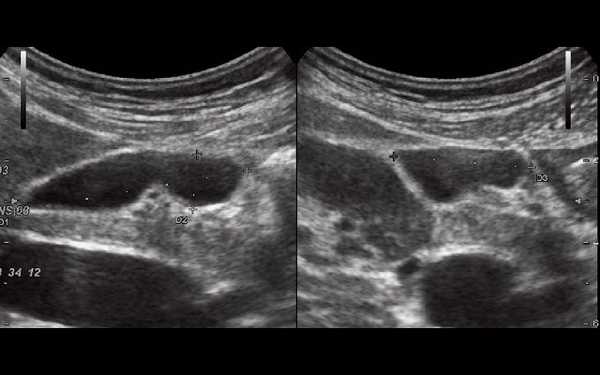

При УЗИ были выявлены диффузные изменения печени и поджелудочной железы, признаки хронического бескаменного холецистита, ангиомиолипома левой почки (без динамики за несколько лет), состояние после экстирпации матки с придатками. В левой подвздошной области соответственно зоне максимальной пальпаторной болезненности на протяжении 9 см отмечалось утолщение стенок толстой кишки до 6-7 мм (рис. 1). Перистальтика кишки отсутствовала, гаустрация была слабо выражена, при этом визуализировалось несколько болезненных при надавливании датчиком выпячиваний пониженной эхогенности, размером от 7 до 20 мм (рис. 2, а, б) с тонкой стенкой до 0,9-1,1 мм и наличием в некоторых из них фрагментов кишечного содержимого и газа (рис. 3, а, б).

Рис. 1. Эхографическая картина дивертикулита. Трансабдоминальное исследование линейным датчиком 7,5 МГц.

"Симптом пораженного полого органа".

Рис. 2. Эхографическая картина дивертикулита. Трансабдоминальное исследование линейным датчиком 7,5 МГц.

а) Продольный срез.

б) Поперечный срез.